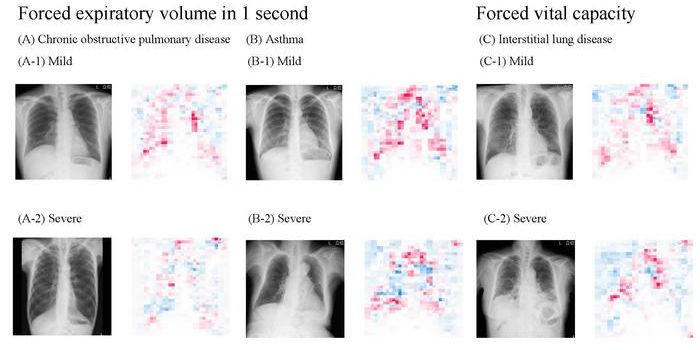

DEC 17, 2024Clinical & Molecular DXDeep learning is a computational tool that is a subset of Artificial Intelligence (AI), and these technologies are often ...